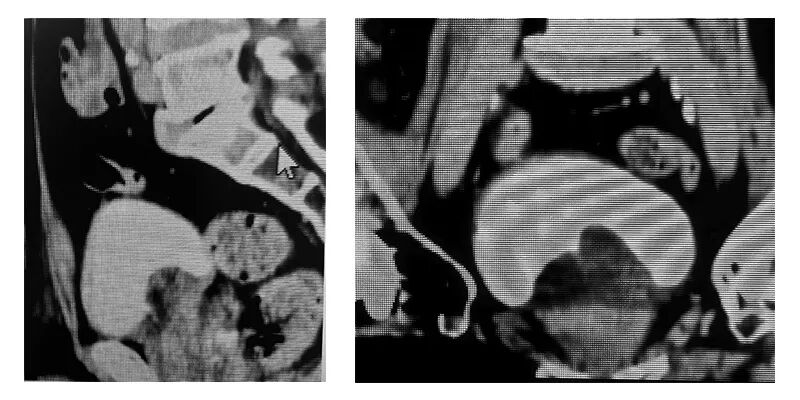

陈生和家属陷入两难,选择了前来湛江中心人民医院泌尿外一科就医,黄海文主任医师团队反复研判患者病情、身体基础及影像学检查结果后,提出了采用腹腔镜前列腺摘除术(Madigan术式)的微创手术方案。该术式无需截石位,恰好适配陈生的体位限制。

经过与家属的充分沟通,在充分术前评估与周密预案后,黄海文主任医师团队顺利为陈生完成手术。术中通过腹腔镜清晰显露前列腺及周围解剖结构,精准完成切除与止血关键操作,全程出血量极少;术后无需膀胱冲洗,在医护团队精心照料下,老人很快恢复顺畅排尿,困扰多年的症状彻底解除。“终于能睡个安稳觉了!”陈生及其家属难掩欣慰。